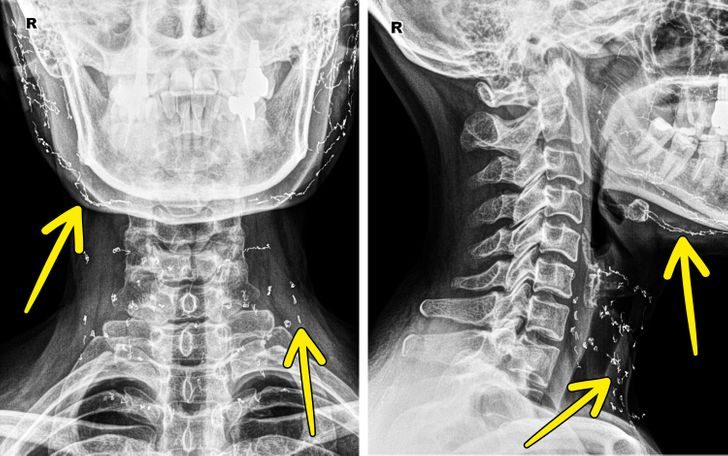

8. Рентгеновский снимок пациентки, которая прошла процедуру подтяжки золотыми нитями